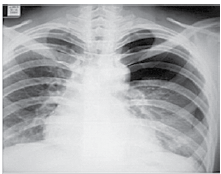

Mulher de 49 anos é internada devido dispneia, febre e dor torácica à esquerda iniciados há 3 dias. Pressão arterial: 110 x 60 mmHg, pulso: 115 bpm; temperatura: 38,3 ºC, frequência respiratória: 26 ipm e saturação arterial de oxigênio: 85%. Radiografia realizada é ilustrada a seguir.

Nesse momento, é correto afirmar: